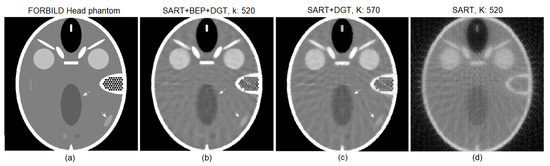

4. Experiments and Results

Low Dosage Tests and Results